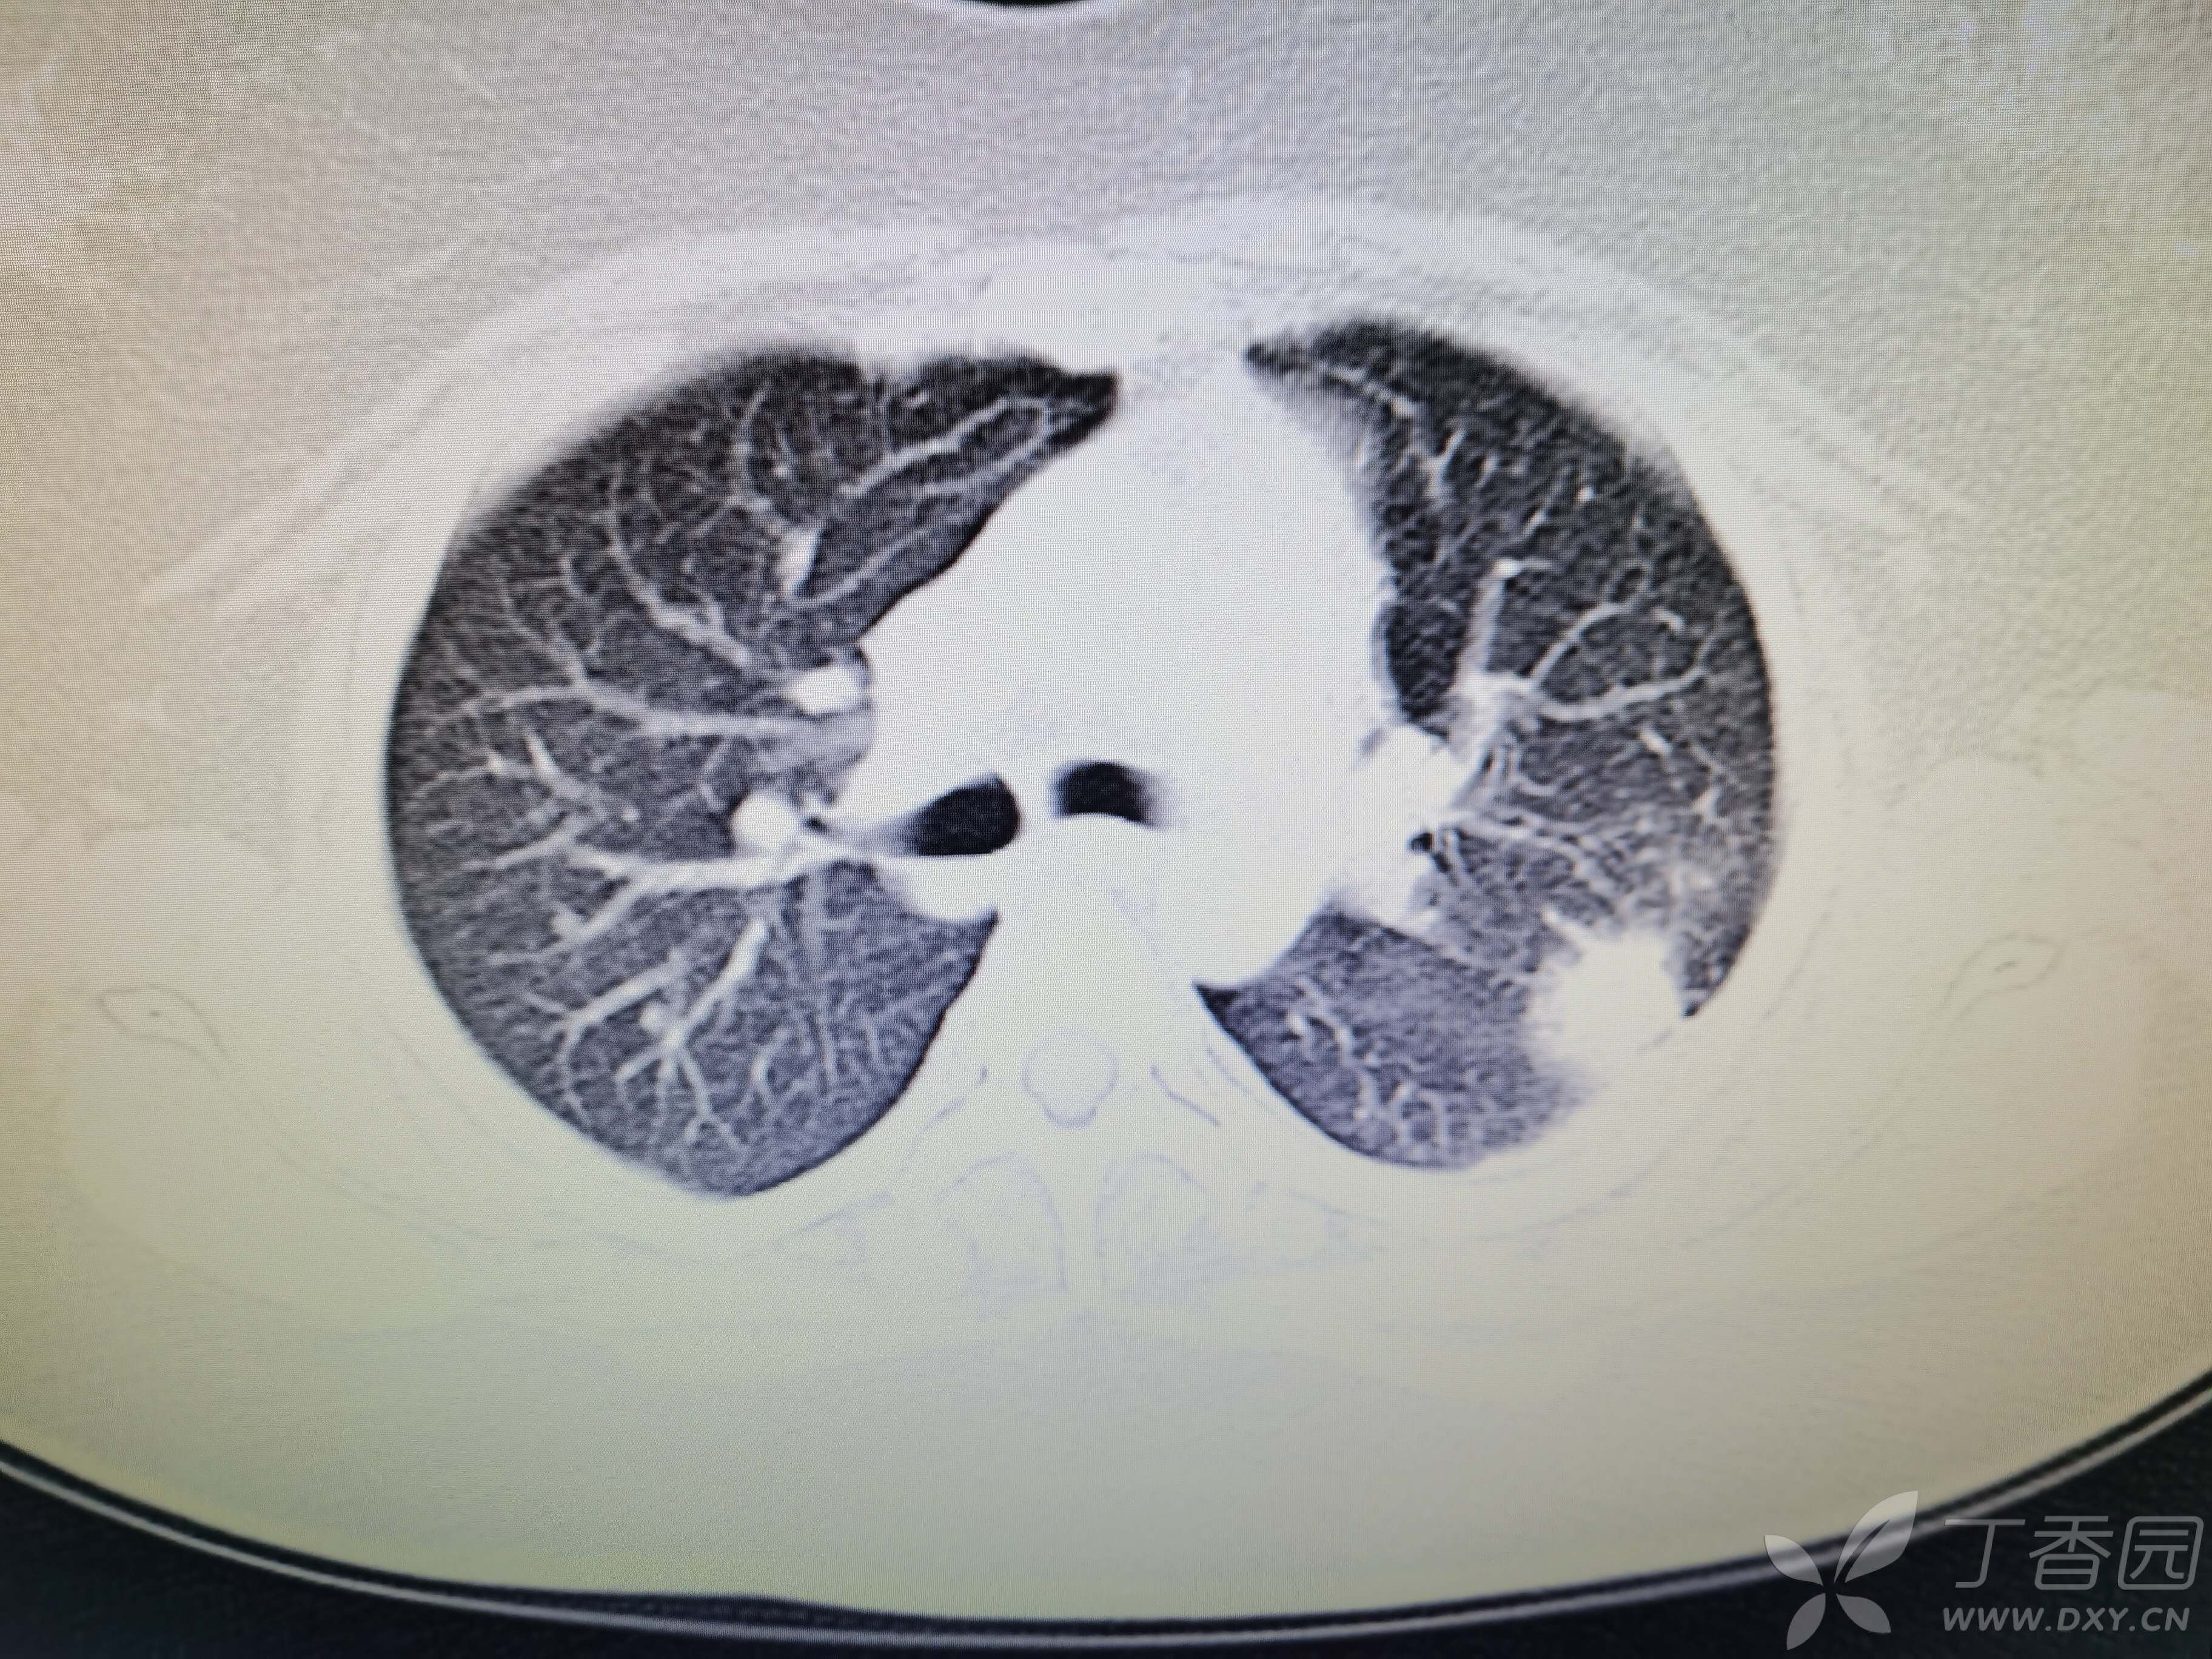

基本信息:女,三十几岁,印度人。。

胸部CT:

如题:猜肺部病灶病理。。